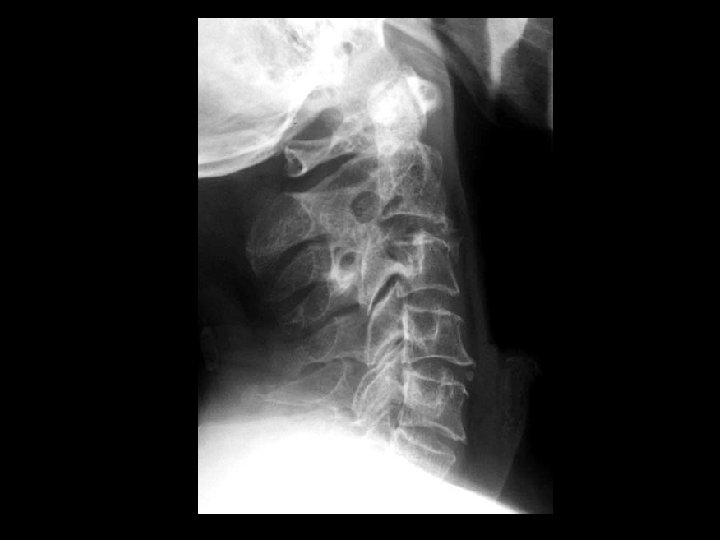

Dens metastasis, pathologic fracture, and C 1 -2 instability • Findings: – 8 mm anterior subluxation of C 1 on C 2 with flexion – Conventional tomogram shows C 2/dens lytic lesion and pathologic fracture • ddx: – Rheumatoid – Dens fracture

C 3 vertebra plana (multiple myeloma) • Findings: – Complete compression of C 3 (look at the vertebral bodies and their corresponding posterior elements!) • ddx: – Metastasis – Kommel’s disease (if see gas and collapse) – EG

Rheumatoid arthritis • Findings: – Destruction of the dens and the anterior C 1 arch by a soft tissue mass – Impression of the anterior thecal sac with slight deformation of the cervical cord • ddx: – Infection – Metastasis